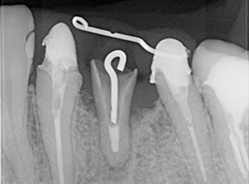

X線

歯科用CTによる3D画像診断